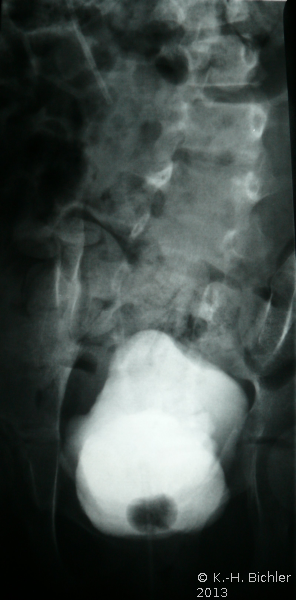

Bei einem 8-jährigen Mädchen mit MMC, ventriculo-peritonealem Shunt und rezidivierenden Harnwegsinfekten ergab die urologische Untersuchung mit Sonographie, AUR, MCU und Urodynamik einen Harnstau II. Grades der linken Niere mit Verplumpung des NBKS (AUR), glatte Abflussverhältnisse rechts (Abbildung 15), VUR links (Abbildung 16b).

Ein VUR war nicht mehr nachweisbar (Abbildung 17ab).